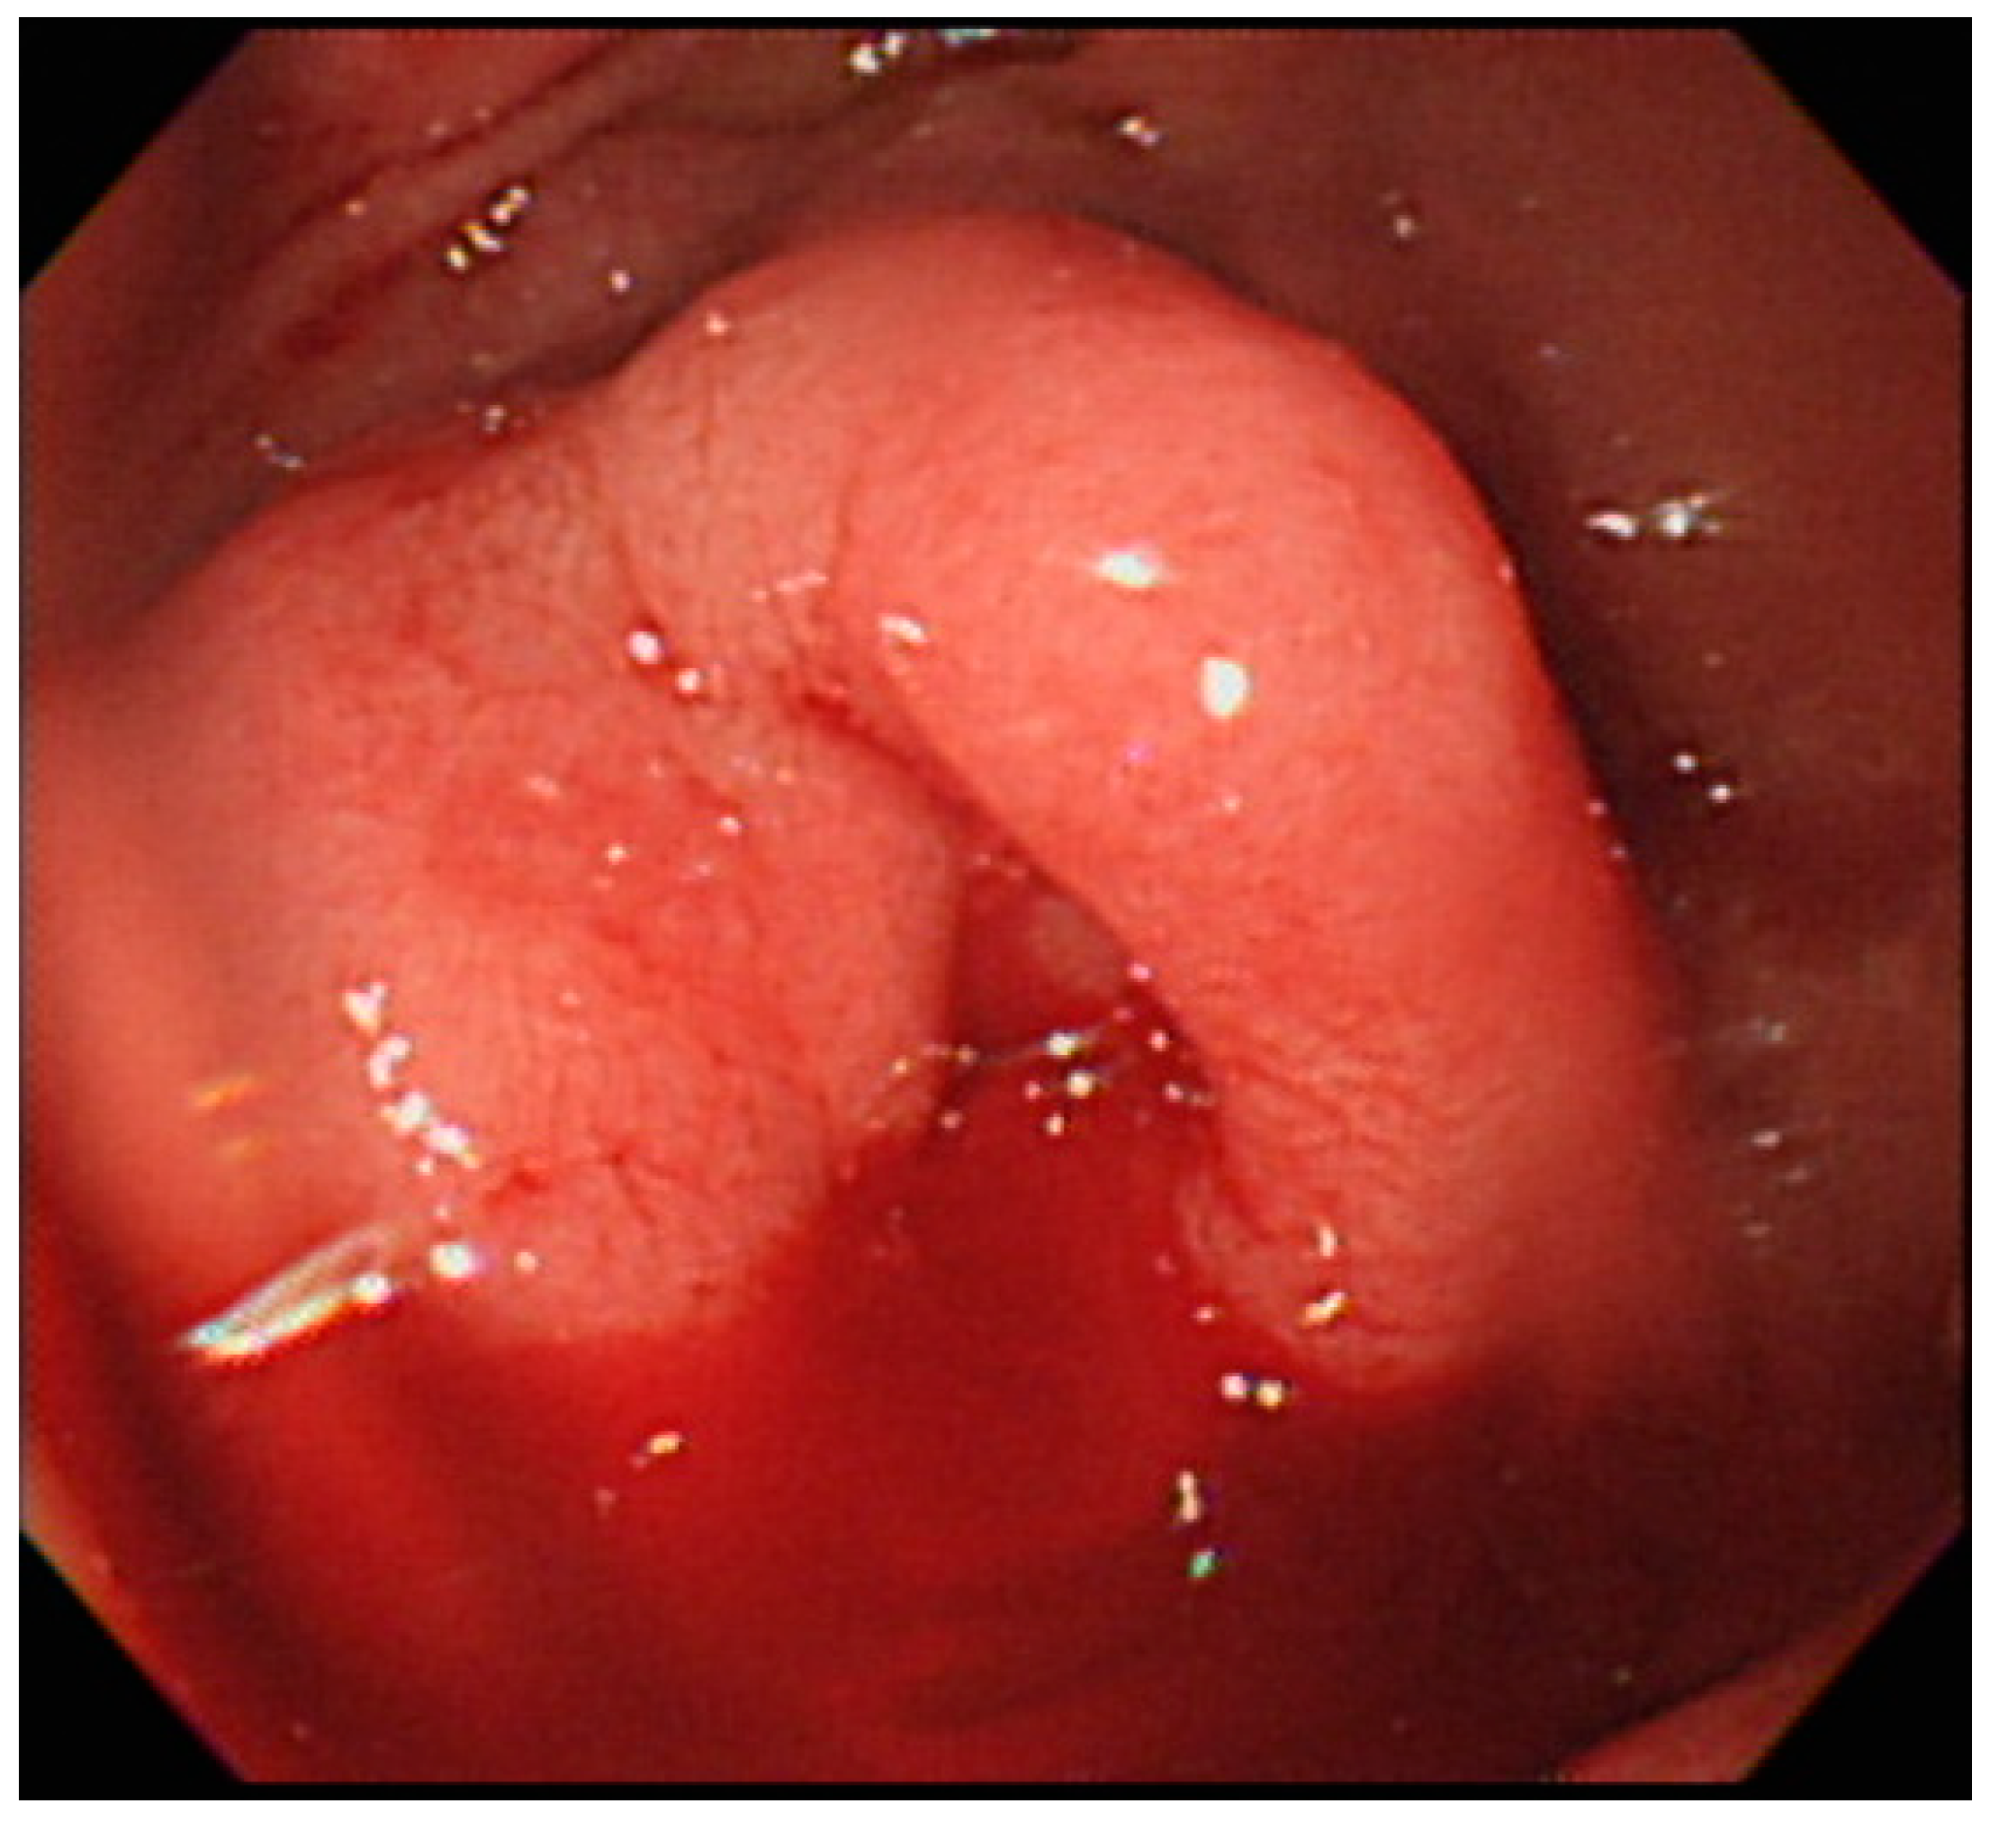

2. Case Report